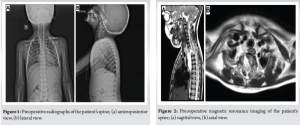

A 4-year-old boy, born to non-consanguineous parents, was evaluated and treated by a pediatrician for three episodes of dizziness lasting a few seconds, during the preceding 7 months. He gave no history of headache, nausea, vomiting, blurred vision, fever, or loss of weight. During his diagnostic work-up, however, a wedge-shaped T1 vertebra was detected (Fig. 1). He was referred to our spine surgery unit for further evaluation and management of the same. On general physical examination, no dysmorphism or cutaneous stigmata of spinal dysraphism were noted. Examination of the cardiorespiratory system and the abdomen revealed no obvious abnormalities. Neurologic examination was also unremarkable with no signs of myelopathy or radiculopathy. His blood cell counts, serum inflammatory markers, serum electrolytes, electrocardiogram, and magnetic resonance imaging (MRI) of the brain were normal.

An MRI of his spine showed hypoplasia and a focal defect of the right half of the T1 vertebral body with an absent pedicle (Fig. 2), through which herniation of a fluid-filled sac (presumed to be dural) measuring 2.3 × 2.4 × 5.2 cm into the pre- and right paravertebral regions from the level of the T1 to T6 vertebral bodies was reported. Partial fusion of T1 and T2 vertebral bodies was noted. No evidence of spinal cord herniation into the sac was noted. Based on these findings, a diagnosis of an isolated anterior thoracic meningocele with intrathoracic herniation was made, and surgery was advised. Under general anesthesia, with the patient supine, a right-sided anterior cervico-thoracic approach was taken. With the assistance of a cardiothoracic surgeon, the manubrium sterni was split along the distal part of the approach. Surgical exposure was carried down to the level of the T5 vertebra. The full extent of the herniated sac was identified and dissected to the base (Fig. 3a).